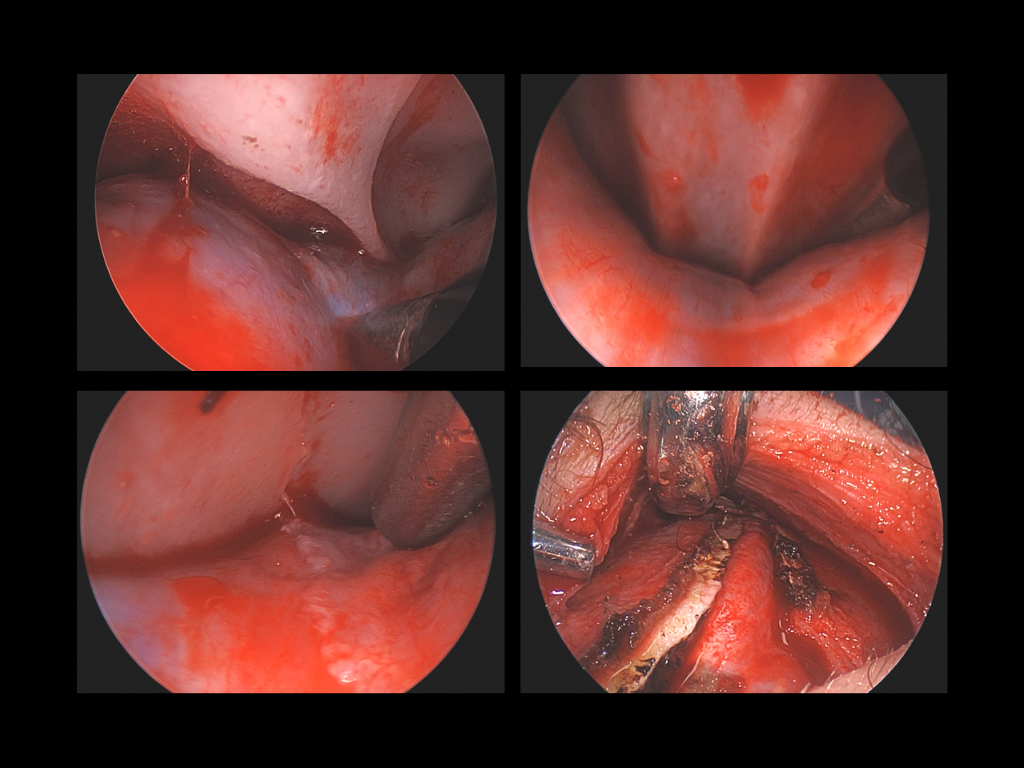

Endoscopic-assisted craniosynostosis surgery is a minimally invasive technique developed to treat infants diagnosed within the first few months of life. Introduced more than two decades ago, this approach allows for safe and early correction of abnormal skull growth by releasing the fused suture through small incisions.

The principle behind the endoscopic method is to use the natural, rapid growth of the infant brain to reshape the skull once the restriction is released. Because the incisions are small and the bone removal limited, this method reduces surgical time, blood loss, swelling, and hospital stay compared to open cranial vault reconstruction.